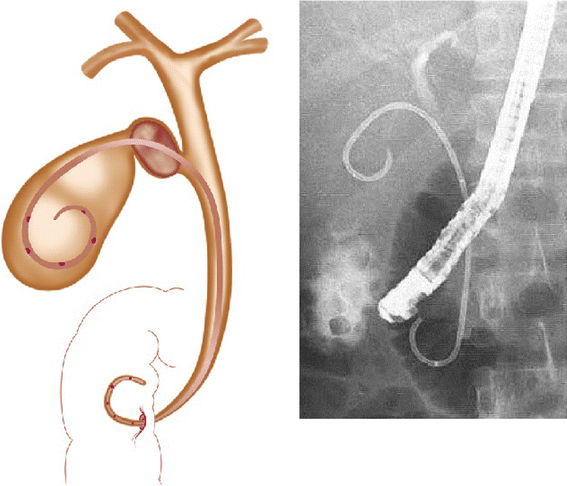

Since endoscopic transpapillary gallbladder stenting (EGBS) requires a difficult endoscopic technique, and relevant case-series studies have been conducted only at a limited number of institutions [29–36], EGBS also has not been established as a standard method. Therefore, it should be performed in high-volume institutes by skilled endoscopists. The procedure is identical to ENGBD, but a 6–10-Fr diameter double pigtail stent is placed (Fig. 4). When 10-Fr stents or a gallbladder stent and a biliary stent are placed (for example in Mirizzi’s syndrome), an endoscopic biliary sphincterotomy is performed to prevent post-ERCP pancreatitis.

Fig. 4

Endoscopic gallbladder stenting (EGBS) procedure. Left Schema of EGBS. Right X-ray shows double-pig tail stent placed in the gallbladder